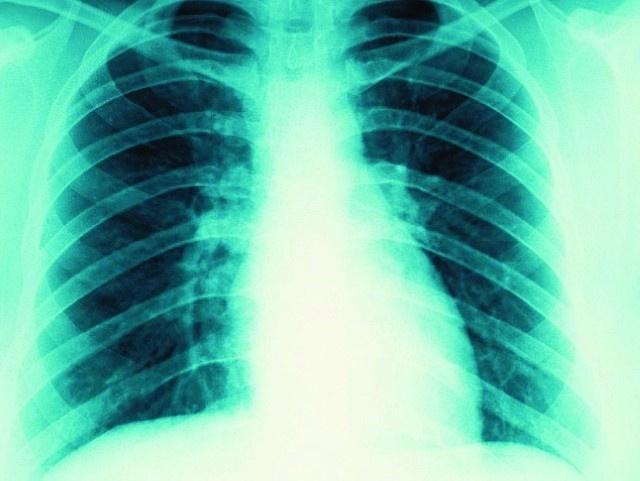

حقق الباحثون في جامعة «إمبريال كوليج» ببريطانيا إنجازاً كبيراً في علاج مرض التليف الكيسي الذي يصيب الغدد المخاطية في الجسم، ويؤثر في وظائف الأعضاء، خاصة الرئتين والجهاز التناسلي، حيث استخدموا الجينات في علاج هذا المرض، وذكرت صحيفة «ديلي ميل» البريطانية أن العلاج الجديد يرتكز على إصلاح جين «CFTR» المعتل في الجسم، من خلال إضافة جين سليم فوقه، ويسبب هذا المرض الفيروسي التهابات متكررة في الصدر بشكل خاص، وقد أظهرت التجارب التي أجريت على بعض المرضى أن هذا العلاج حقق نتائج جيدة.

يشار إلى أن التليف الكيسي يصيب أكثر من 10 آلاف شخص في بريطانيا وحدها، ولا يوجد له علاج في الوقت الحالي.